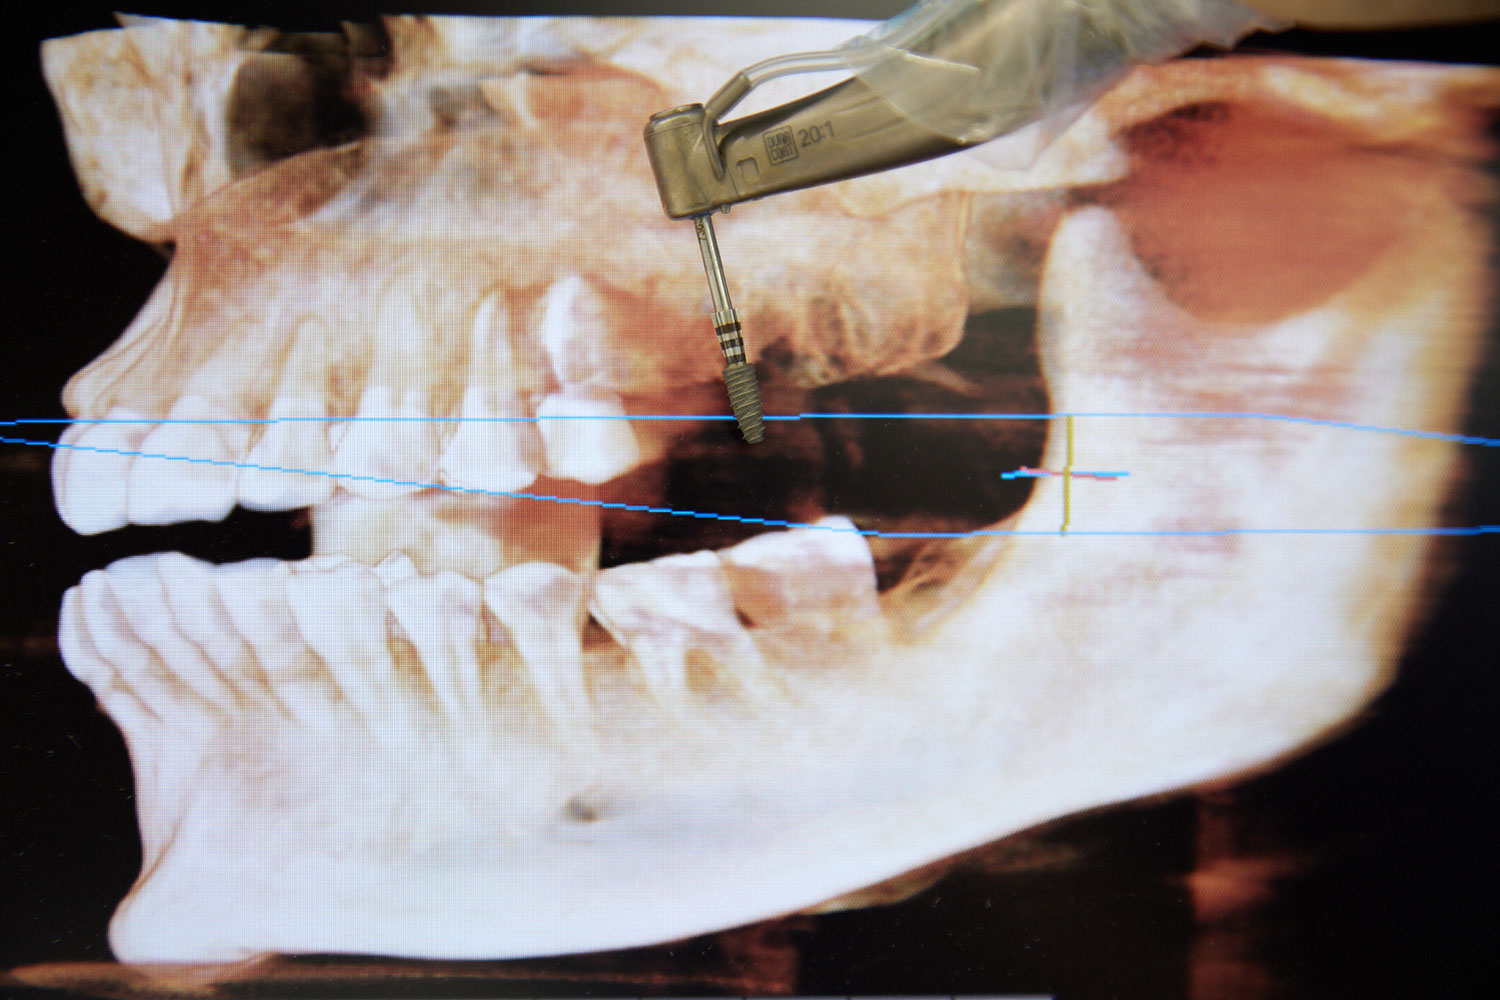

Un implant dentaire est comme une petite vis, c’est une racine artificielle, il est en titane et biocompatible. Il sert à remplacer la racine d’une dent abîmée ou manquante et permet de servir de point d’ancrage à une future prothèse dentaire ou couronne céramique. Que ce soit pour une ou plusieurs dents manquantes nous vous proposerons la solution la mieux adaptée à votre cas, pour un résultat optimal à la fois esthétique et fiable dans le temps.

Il n’y a pas d’âge plafond, mais un bilan pré-implantaire est indispensable. Une imagerie 3D permet d’évaluer la qualité et le volume osseux.

Le volume osseux se mesure précisément grâce au cone beam. En cas de déficit, des techniques comme le comblement osseux (sinus lift) ou des greffes peuvent être proposées.